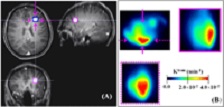

• Wei Huang is using advanced quantitative MRI techniques, including the OHSU AIRC-developed Shutter-Speed dynamic contrast-enhanced (DCE) MRI method, to (1) improve breast cancer diagnostic accuracy and reduce unnecessary biopsy procedures on women with benign lesions and (2) predict breast cancer response to neoadjuvant chemotherapy.  Furthermore, Wei Huang and his collaborators are exploring ways to integrate MRI markers with clinical, genetic, and histopathological markers to significantly improve the power of accuracy in predicting cancer response to treatment, an important step towards achieving precision medicine for individual cancer patients.  The Figure at right (click the image to enlarge) demonstrates that, using DCE-MRI markers Ktrans (rate constant for contrast agent transfer between blood vessel and tissue), ve (extravascular and extracellular volume fraction), and τi (mean intracellular water lifetime), we can predict whether a breast cancer patient responds to neoadjuvant chemotherapy or not after only one cycle of a 6-8 cycle chemotherapy course, which usually lasts 4-5 month long.  The substantial decrease in tumor Ktrans and increases in tumor ve and τi from pre-treatment MRI at visit 1 (V1) to MRI after one cycle of chemotherapy at visit 2 (V2) are clearly visible for a responder (Figure A), while there are no noticeable changes in these markers in a non-responder (Figure B).